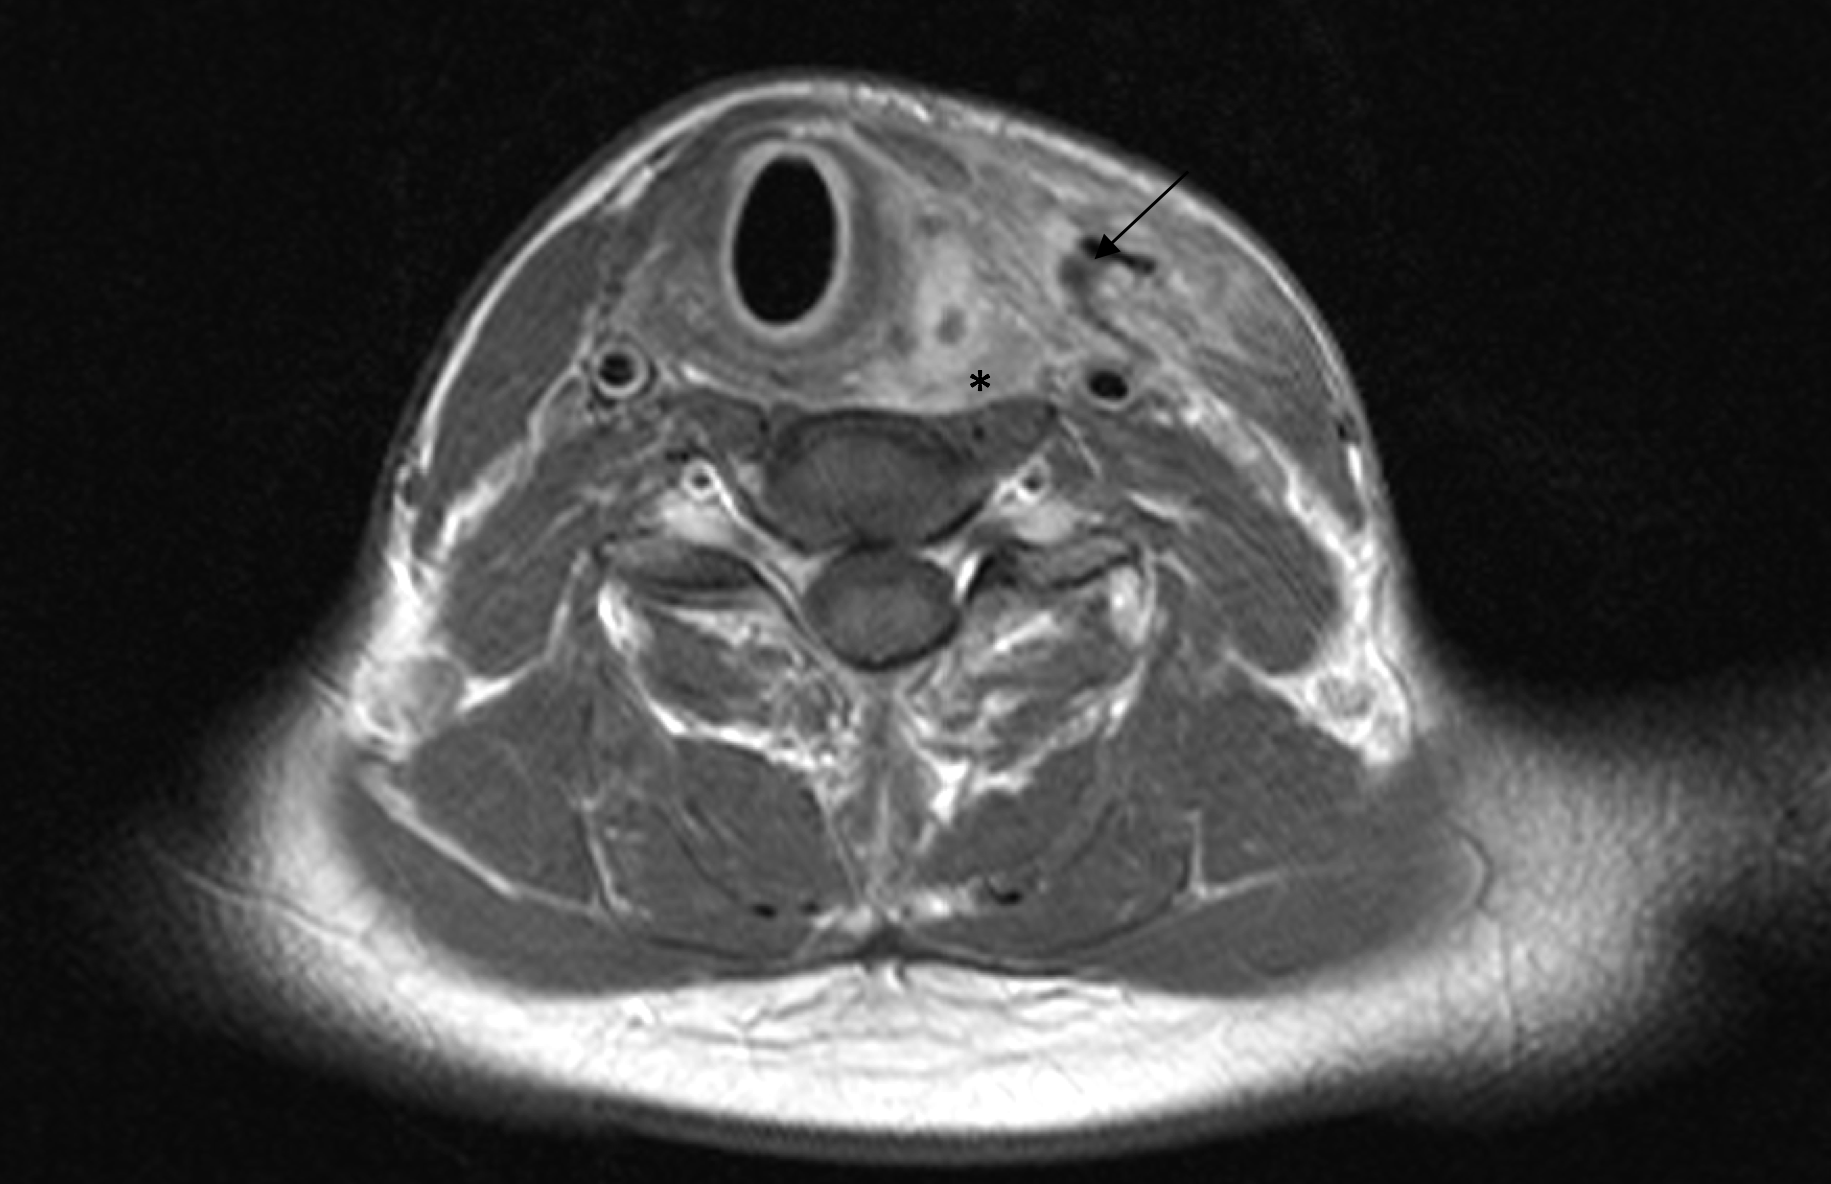

Preoperative ultrasonographic findings showed an oval hypoechoic inhomogeneous mass, approximately 4 x 3 x 1.5 cm in levels III to IV of the left side of the neck below the sternocleidomastoid muscle. (Fig. 1) The mass was partly indistinct to the adjacent tissue and demonstrated peripheral perfusion with no central vascularity. (Fig. 2) The surrounding soft tissues appeared oedematous and thickened. (Fig. 1 – 2)

The patient received intravenous antibiotic therapy with amoxicillin /clavulonic acid for 3 weeks. During the course, a MRI of the neck was performed, which showed residual fluid in the former abscess cavity and another fluid collection in the left thyroid lobe, which appeared to be in contact. (Fig. 5) A sonographic check showed an echo-poor area around the left thyroid lobe corresponding to the MRI findings (Fig. 6). Owing to these findings and continued secretions from the wound area, revision surgery with wound drainage was carried out. Healing and improvement was confirmed on a subsequent sonographic check. (Fig. 7)